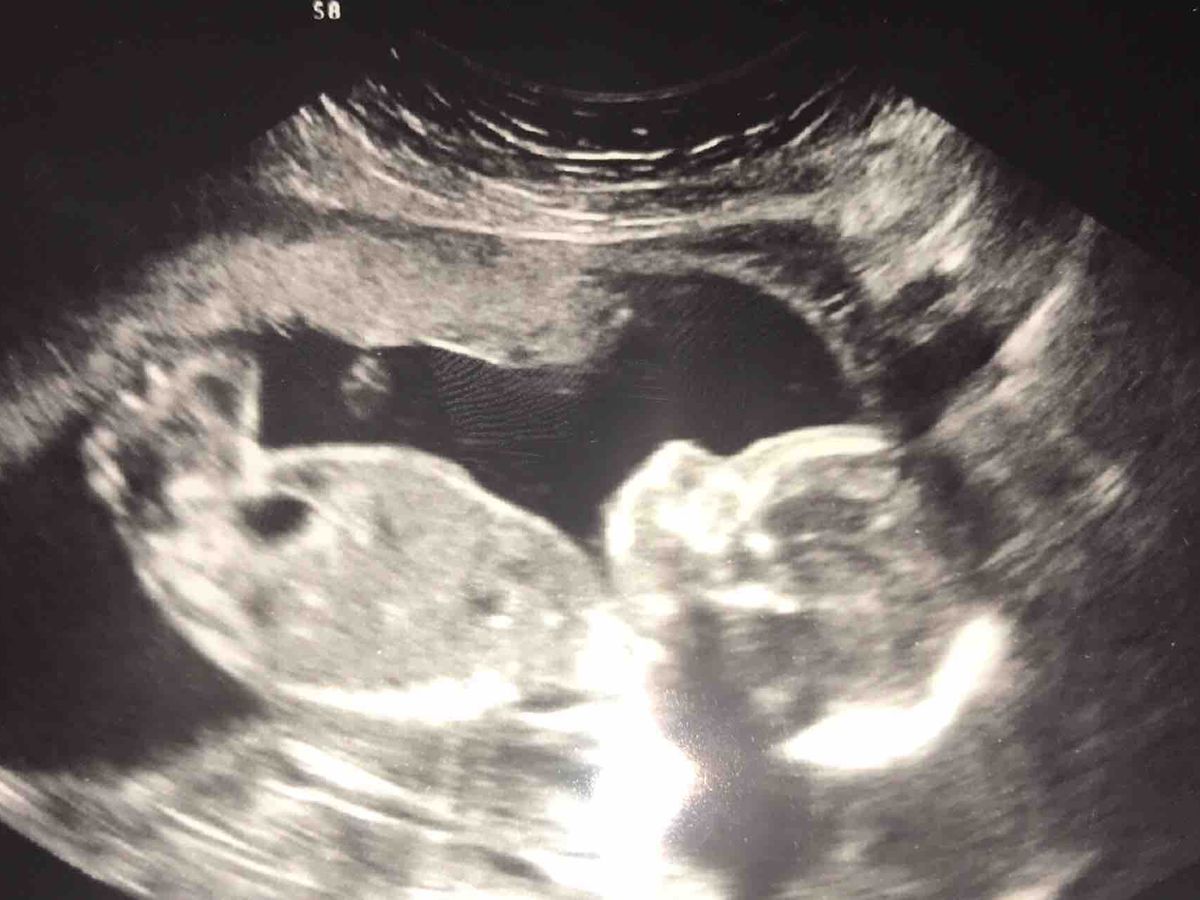

As I’m sure most of you are aware that my sister Devon & her partner Aaron are expecting their first child together in May. I am completely over the moon to tell everyone that we are having a boy!! (I say we as I feel like their baby is mine as I love him so much already).

When Devon & Aaron went for the 20week scan to find out the gender of their baby they received some very unfortunate news that he has various problems with his heart amongst other things. Devon are Aaron were then referred to the Royal Victoria Hospital in Belfast to see a heart specialist so they could get a better understanding of the conditions that their baby has.

In weeks to come they discovered that Baby Knights problems became more and more complex, they became aware of this after numerous appointments with the consultants, they are as follows;

Dextrocardia

Right atrial isomerism

AVSA and common AV valve with a double outlet

Stomach on the left hand side of his body

And an enlarged liver

Devon & Aaron are unsure of the amount of time they will get to spend with their baby boy once he arrives, every minute will count & we all cannot wait to meet him. As Devon's sister I have decided to appeal to everyone through a 'Go Fund me page' so we can raise money for the British heart foundation, the Neo Natal Unit in the Royal Victoria Hospital & help towards any costs for Baby Knights funeral. Any amount of donations would be extremely helpful & we would all be eternally grateful.